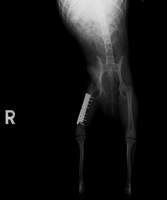

この子も他院の紹介です。アクシデントにより、大腿骨(太もも)骨折で来院されました。昨年、手術を行いましたが、元気な子なのでプレート自体が折れてしまいました。

再手術によりプレート(ダブル)が安定し、今では普通にしている様子。チタンを使用していますが、骨折端の骨吸収がないかどうかの定期チェックです。

すでに半年が経ち、問題なさそうです。元気な子なので、普通に歩けることが幸せそうです。よかったね、ルフィちゃん!